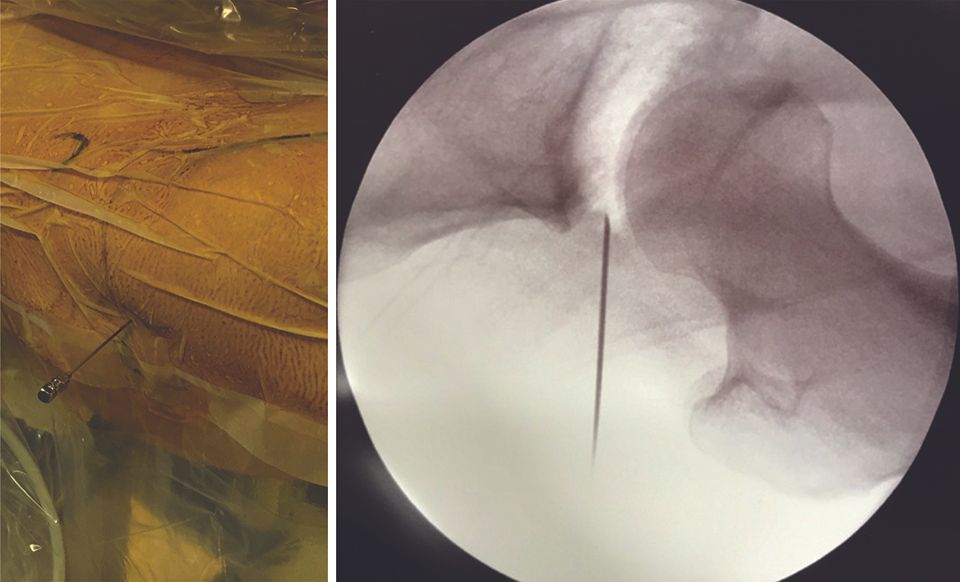

Anterolateral or anterior paratrochanteric portal

The entry point in the skin is made where the line passing over apex of the greater trochanter (perpendicular to the ASIS–patella line) intersects with the line mapping the anterior edge of the femur. This point is situated approximately 1 cm above and 1 cm in front of the greater trochanter (Fig. 3, left). Using the image intensifier, if the patella is facing up, the needle will be parallel to the floor and pointed towards the clear space in the separated joint (Fig. 3, right).

Intra-articular infusion of 10–20 ml of physiological serum negates the retentive effect of the labrum (36,37).

This technique, coupled with general anaesthesia and a neuromuscular blocker to aid the relaxation of the anterior iliofemoral ligament, allows a reduction in traction force (joint separation) from 500 N to 230–300 N (38,39), thus reducing the risks of potential complications (see “Complications”, above). Next, the nitinol guide is inserted into the spinal needle (Fig. 4). After withdrawing the spinal needle, the hollow trocar is introduced on the nitinol guide (Fig. 5) and the arthroscope is inserted. The arthroscopic view is shown in Figure 6.

As regards anatomic structures, the portal passes through the fascia lata and the gluteus medius.